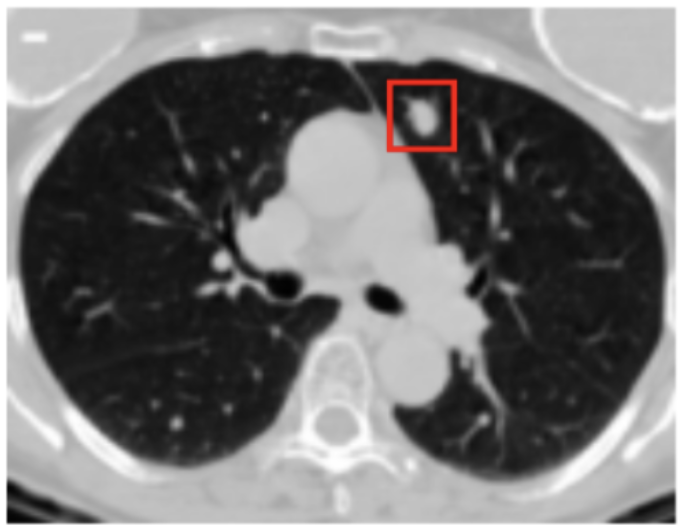

Before we dive deeper into enforcing causal alignment, we have to get to know the data we're working with. Our images are slices of lung CT scans which might or might not contain malignant lung nodules.

- x: The image

- y: The image's label. y=1 means there is a malignant nodule, y=0 means there is no malignant nodule.

- m: The doctor-annotated area where the nodule is. Annotated as a red box in the image.

We are trying to construct a function f which looks at our image x and determines the correct label y. To ensure causal alignment, we also want to make sure that f is "paying attention" to the abnormal area m, and not some other part of the image.